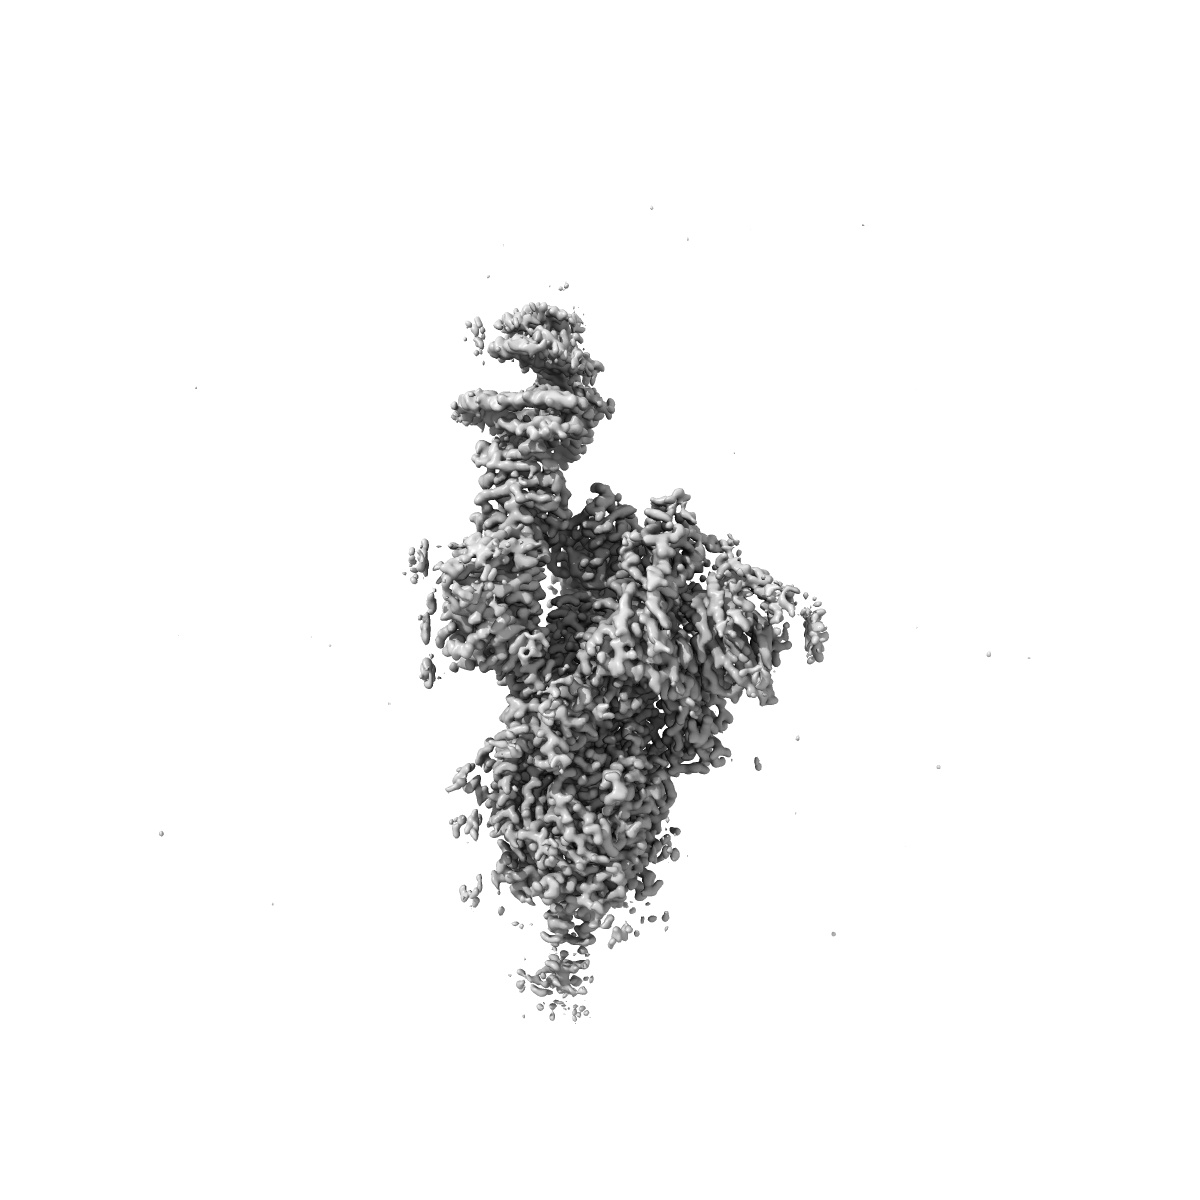

SARS-CoV-2 Omicron Variant SPIKE trimer complexed with ACE2

Single-particle2.77 Å

Sample: SARS-CoV-2 Omicron Variant SPIKE trimer complexed with ACE2

Structures of the Omicron spike trimer with ACE2 and an anti-Omicron antibody.